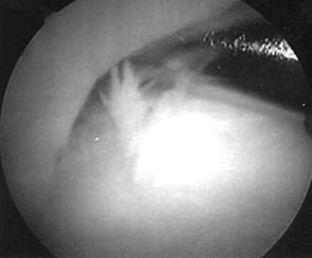

We evaluated an all arthroscopic technique for treating suprascapular nerve entrapment by cyst formation in the spinoglenoid notch. Eight patients showed positive MRI and EMG findings with clinical sign of weakness and pain and with atrophy of the muscle. All patients underwent an all-arthroscopic procedure. The patients were evaluated preoperatively and 6 weeks and 3 months postoperatively and for the latest follow-up by clinical examination, MRI, and EMG. All patients improved in terms of pain, strength, and function. We found six superior labrum anterior and posterior (SLAP) lesions. In these patients the cyst was drained, and the SLAP lesion was repaired. In two patients there was no communication between the joint and the cyst, and therefore capsulotomy was performed and left open. The results of our study show that arthroscopic decompression of the suprascapular nerve can be achieved by an all arthroscopic technique if the cyst formation is located at the spinoglenoid notch.

Fig. 3